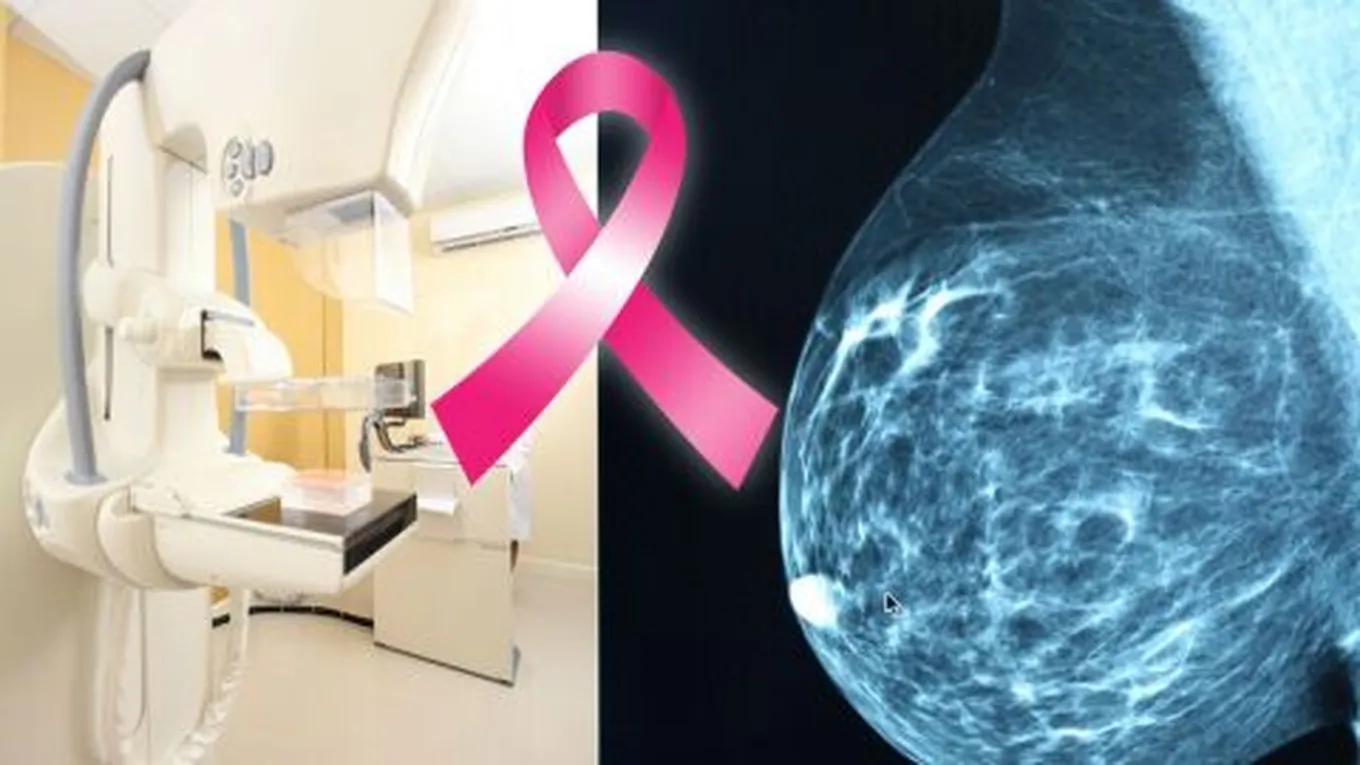

- الماموجرام: حيث يتم الكشف عن سرطان الثدي بالأشعة السينية من خلال استخدام جهاز الماموجرام، فإذا لوحظ وجود خلل في الصورة يوصي الطبيب بإجراء فحص الماموجرام التشخيصي.